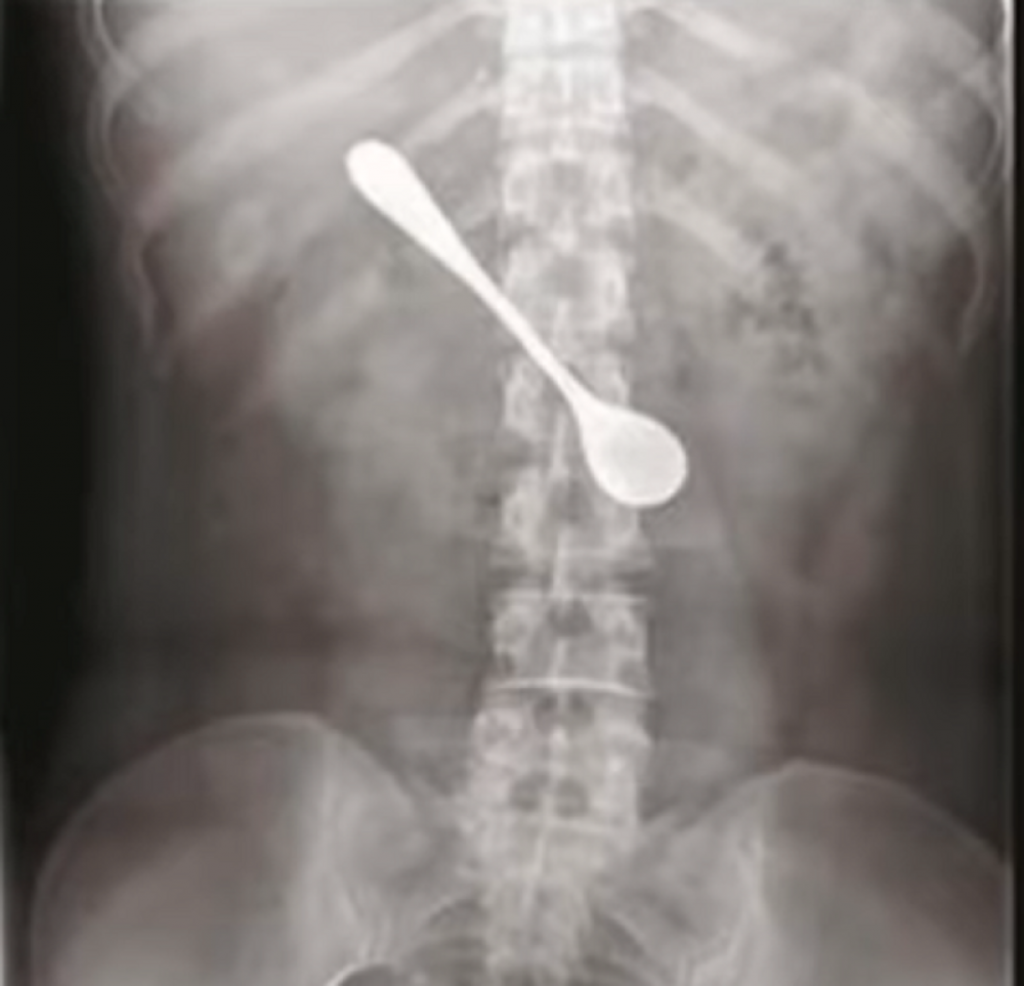

Pacijentkinja poznata kao Lili progutala je kašiku dužine 13 cm. Prošlo je četiri dana pre nego što je potražila lekarsku pomoć, jer pre toga nije osećala nikakvu bol i nelagodu, prenose kineski mediji.

Nakon rendgenskog snimanja i endoskopije, doktori su uspjeli da joj izvade kašiku iz tijela.